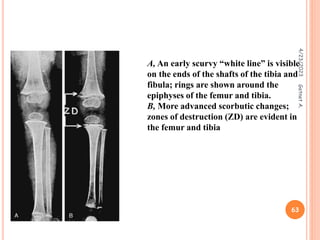

 characteristic clinical picture, the radiographic

appearance of the long bones, and a history of poor

vitamin C intake.

 distal ends of the long bones (knee)

 Radiological changes – simple bone atrophy ,ground

glass apperance ,thin cortex ,white line of fraenkel ,

 Dx – zone of rarefaction under the white line at the

metaphysis

A, An early scurvy “white line” is visible

on the ends of the shafts of the tibia and

fibula; rings are shown around the

epiphyses of the femur and tibia.

B, More advanced scorbutic changes;

zones of destruction (ZD) are evident in

the femur and tibia